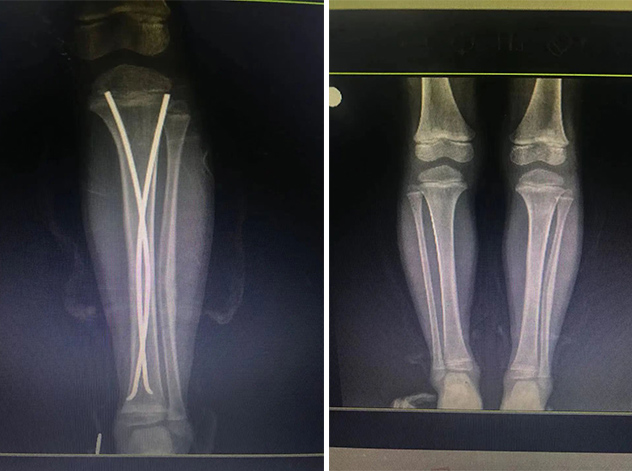

經(jīng)拍片顯示,睿睿左脛腓骨中段粉碎性骨折。接診的我院骨科中心主任羅軍建議其入院接受手術(shù)治療。

術(shù)前

拆前拆后對(duì)比